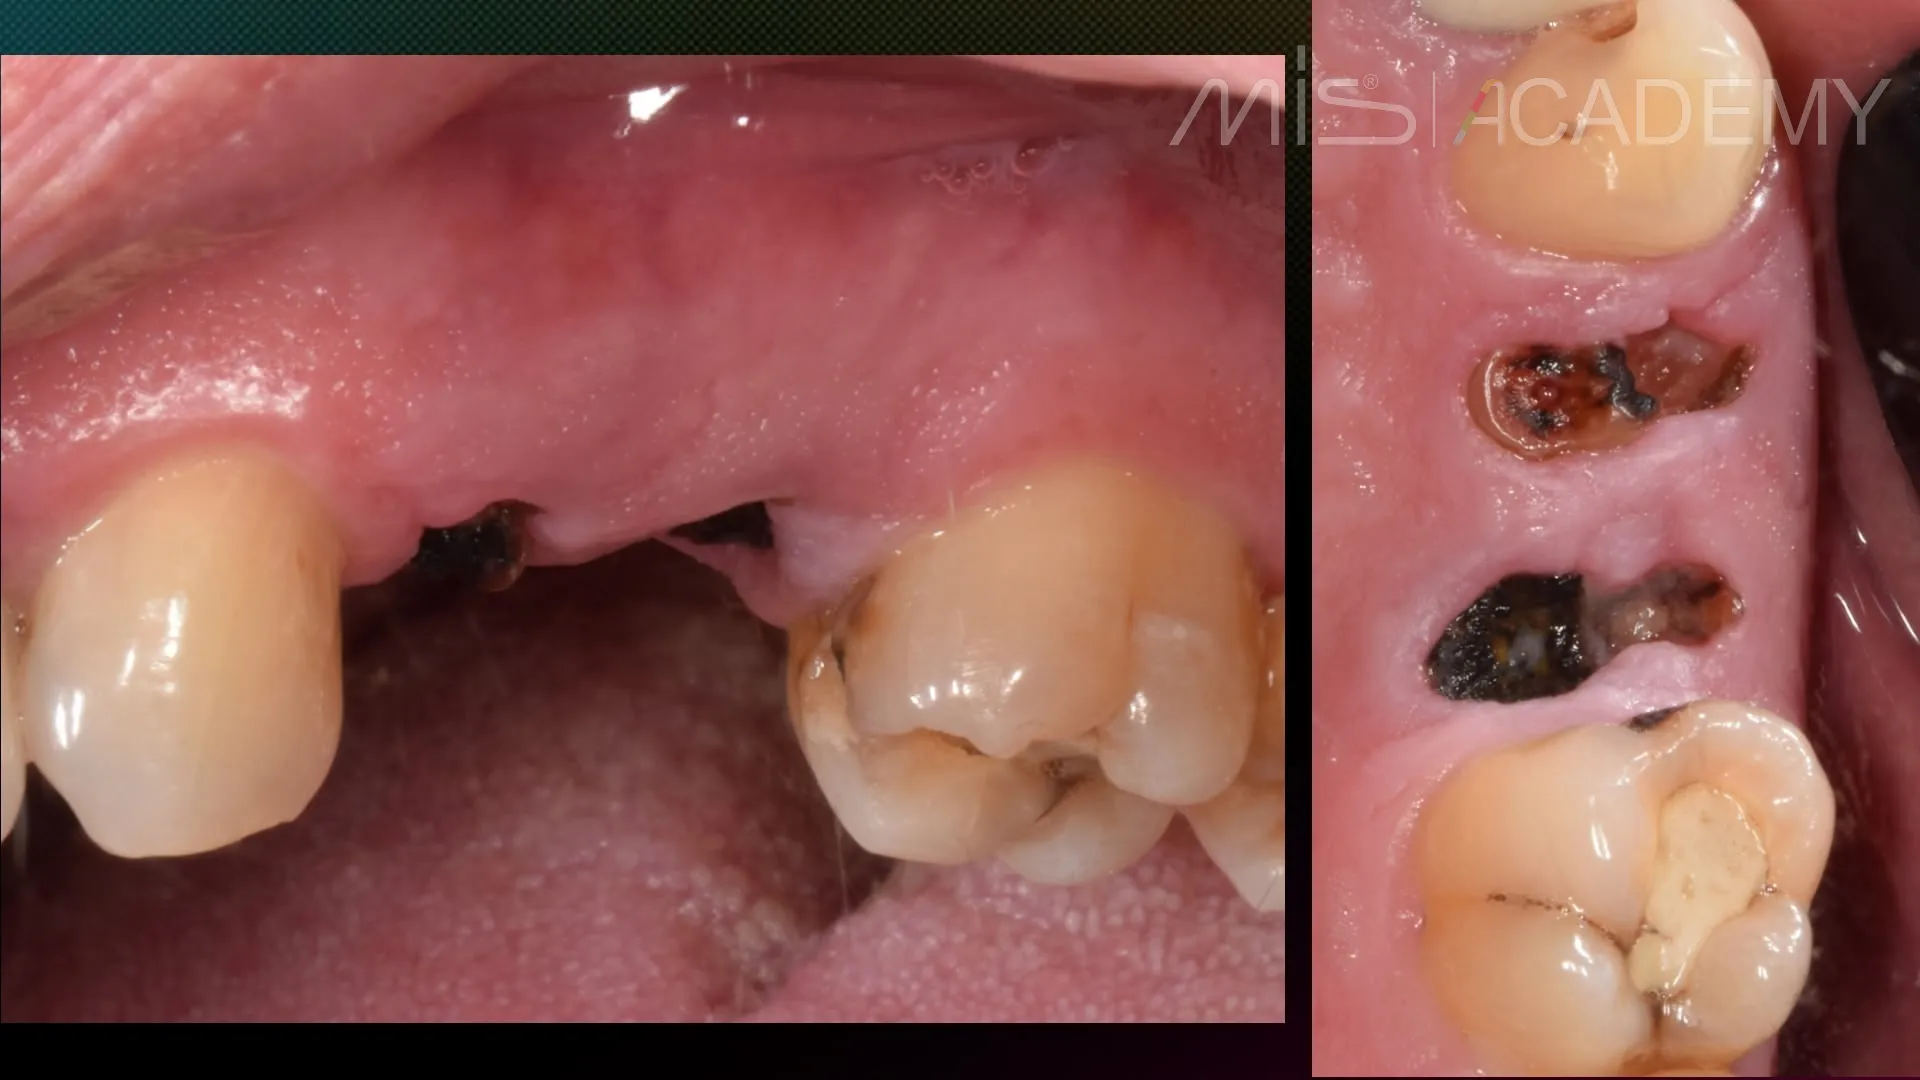

Промежуточный этап лечения пациента:

— Удаление корней 2.4, 2.5.